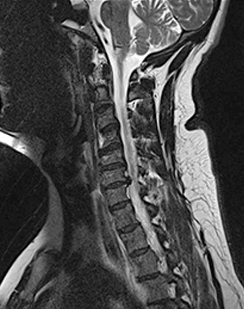

목 디스크 (경추 수핵 탈출증)

경추 추간판(목 디스크)의 수핵이 빠져나와 신경뿌리나 척수를 누르게 되어

통증을 유발하고 심한 경우에는 어깨나 팔에 힘이 빠질 수 있습니다.